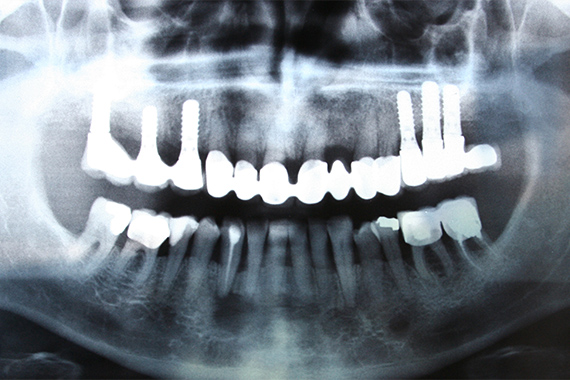

インプラントは、歯が抜けた部分の骨に人工の歯根を埋め込み、その上に人工歯を装着する治療方法です。見た目や機能が天然歯に近いのが特徴です。ブリッジや入れ歯のように、周囲の健康な歯に負担をかけず、金属アレルギーのあるかたでもご使用いただけます。また、メンテナンスをしっかり行うことで長くお使いいただけます。愛知県岡崎市美合町・美合駅前にある当院ではインプラント治療も行っておりますで、ご興味のあるかたはご相談ください。

先進設備を使用することで、顎の骨の形状などを立体的に正確に把握できるため、神経や血管を避けた安全な治療計画を立てることが可能になります。また、インプラントを埋入する位置・角度・深さを正確に誘導するためのガイドを使用して、手術の安全性と成功率が向上するよう努めております。

診査・診断

お口の状態を正確に確認するために歯科用CT撮影を行います。骨の状態や噛み合わせ、神経・血管などを精密に確認し、患者さん一人ひとりに適した治療計画を立てます。